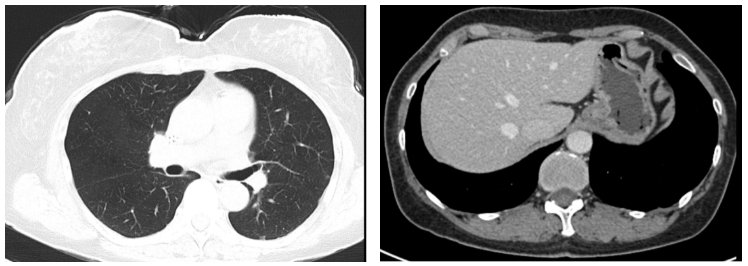

图1. 2018.11肝左叶转移灶

图3. 2019.03两肺转移灶(左图),肝左叶转移灶(右图)